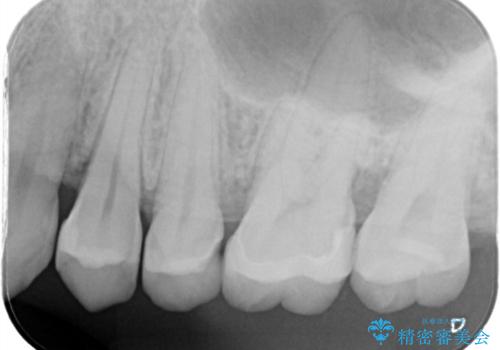

- 歯が欠けたということで来院された患者様です。

診断した結果、昔つめたプラスチックの材料が劣化し割れてしまったことが原因でした。

そのためセラミックれの治療を進めました。

前詰めていたやつをきれいに取り、セラミックにすることによって適合のいいものになりました。色も満足していただけました。